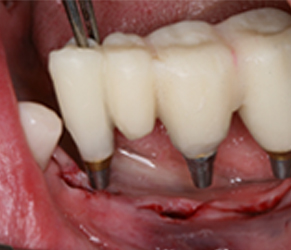

가이드 수술

분석한 정보로 보조장치와 보철물을 정밀하게 제작하여 임플란트 수술에 적용합니다.

즉시 보철

잇몸을 절개하지 않고 임플란트를 식립하며, 당일에 보철이 가능합니다. (뼈 상태에 따라 치료기간이 길어질 수 있습니다.)